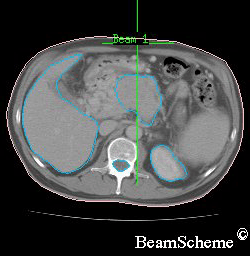

This picture shows a typical CT scan cross section (slice). The slice shown is of the bottom of the rib cage. Note that the left on this scan is actually the right side of the body.

This is what you can see:

on the left is a large crescent – this is the liver

on the right, at the bottom, is a round shape – this is the kidney

in the centre, at the bottom, is a lighter round shape – this is the spinal cord inside the backbone

in the middle is an irregular shape, which is the pancreas with a cancer inside it